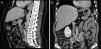

Perante as características morfológicas e imunohistoquímicas, o diagnóstico efetuado foi de um linfangioleiomioma ganglionar. Considerando que o envolvimento extrapulmonar exclusivo é raro5, procedemos à revisão da lobectomia, realizada 14 anos antes por bronquiectasias complicadas de quilotórax. Foi também observada uma proliferação pulmonar nodular intersticial de células fusiformes, inicialmente interpretadas como MPMNs, secundários a hipoxémia local, mas revelando diferenciação muscular com positividade para α-SMA, que não se encontra reportada nesta entidade7. Um dos gânglios linfáticos hilares também mostrava pequenas áreas musculares lisas subcapsulares com imunomarcação para HMB-45. A paciente não exibia o aspeto radiológico típico da LAM na primeira cirurgia, mostrando apenas alterações compatíveis com bronquiectasias e derrame pleural. Em 2008, apesar de ter desenvolvido dispneia de esforço, não foram reportadas alterações consistentes com envolvimento pulmonar por LAM (fig. 6). No entanto, avaliando as imagens retrospetivamente e perante um diagnóstico patológico estabelecido de linfangioleiomioma, poderão ser valorizadas de forma diferente raras lucências visíveis, algumas envolvidas por opacidades em «vidro despolido» ligeiras. Estas assemelhavam-se a quistos pulmonares (com uma parede discernível, que é contrária à hipótese de apenas se tratar de destruição pulmonar enfisematosa). Estes eram bem definidos, com pequenas dimensões, similares uns aos outros e dispersos pelos pulmões. Estas alterações são muito ligeiras, não permitindo um diagnóstico imagiológico inequívoco da doença, mas que também não devem ser ignoradas ou desconsideradas, e podem corresponder, de facto, ao comprometimento pulmonar inicial e ligeiro pela LAM. A TC abdominal mostrou também massas consistentes com dilatação de vasos linfáticos abdominais e com gânglios linfáticos aumentados (fig. 7).

Imagens TAC axiais com algoritmo de alta resolução do tórax (B, D) e imagens TAC axiais de alta resolução (A, C): algumas lucências visíveis (círculos azuis) de pequenas dimensões, semelhantes umas às outras e distribuídas ao longo dos pulmões, bem definidas com uma parede discernível, algumas delas rodeadas por ligeiras opacidades em vidro despolido (C).